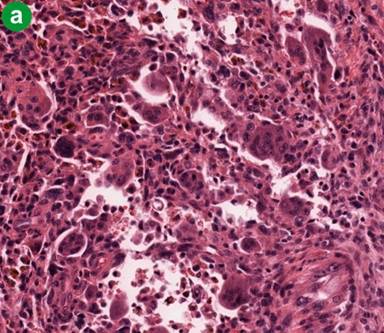

Microscopy revealed that the main bulk of the tumor was cystic/hemorrhagic and located within the uncinate process. At the same time, the tumor was intimately related to the main pancreatic duct and its branches. It grew along their lumen as an intraductal, pencil like growth and protruded into the lumen of the duodenum, forming a polypoid structure. Both components (cystic and intraductal) were predominantly comprised of non-epithelial component: pleomorphic large cells, histiocyte-like mononuclear cells, atypical mononuclear cells and spindle cells with multiple, atypical and bizarre mitoses, as well as osteoclast-like giant cells (Figure 3a). Extensive sampling of the tumor revealed a minor epithelial component (Figure 3bcd), showing glandular differentiation within the intraductal pencil-like growth present in the main pancreatic duct and its branches (Figure 3ef), as well within the cystic component.

Figure 3. Histomorphologic findings. a. Mixture of the pleomorphic large cells, histiocyte-like mononuclear cells, atypical mononuclear cells and osteoclast-like giant cells (H&E, original magnification 20x). b. As above, but mixed with epithelial neoplastic cells (H&E, original magnification 20x). c. and d. Epithelial neoplastic cells strongly positive for pankeratin and cytokeratin 34 beta E12 (original magnification 20x). e. Early intraductal growth of the undifferentiated carcinoma of the pancreas (H&E, original magnification 2x). f. Pancreatic duct almost completely occluded by intraductal growth of the undifferentiated carcinoma of the pancreas (H&E, original magnification 2x). |